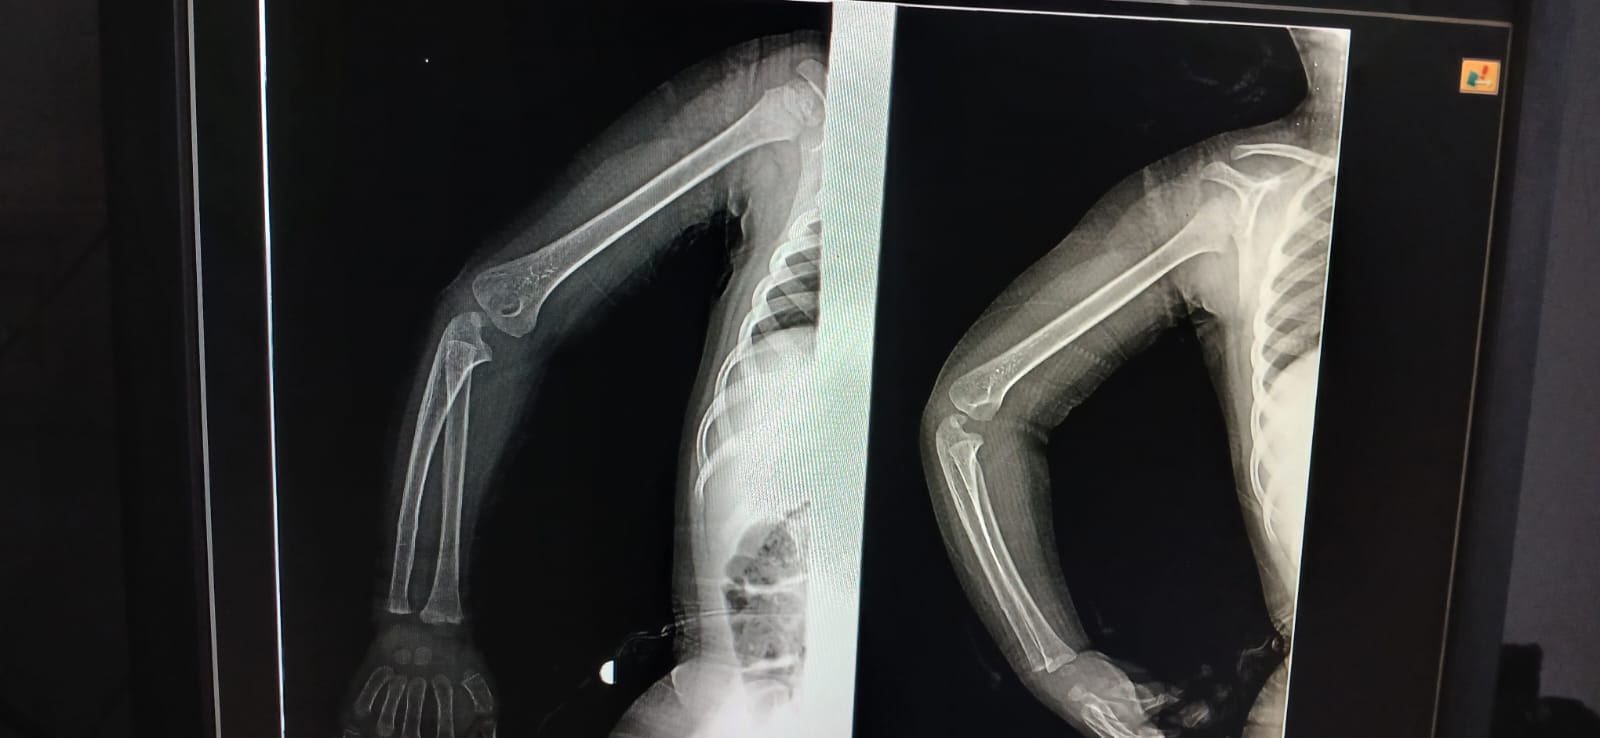

بنتى 3 سنين وقعت على ايدها من الركنه فى البيت

بنتى 3 سنين وقعت على ايدها من الركنه فى البيت في ورم بسيط تحت المفصل والم فى دراعها

WhatsApp Image 2026-03-16 at 9.17.26 AM _1_ WhatsApp Image 2026-03-16 at 9.17.26 AM _2_